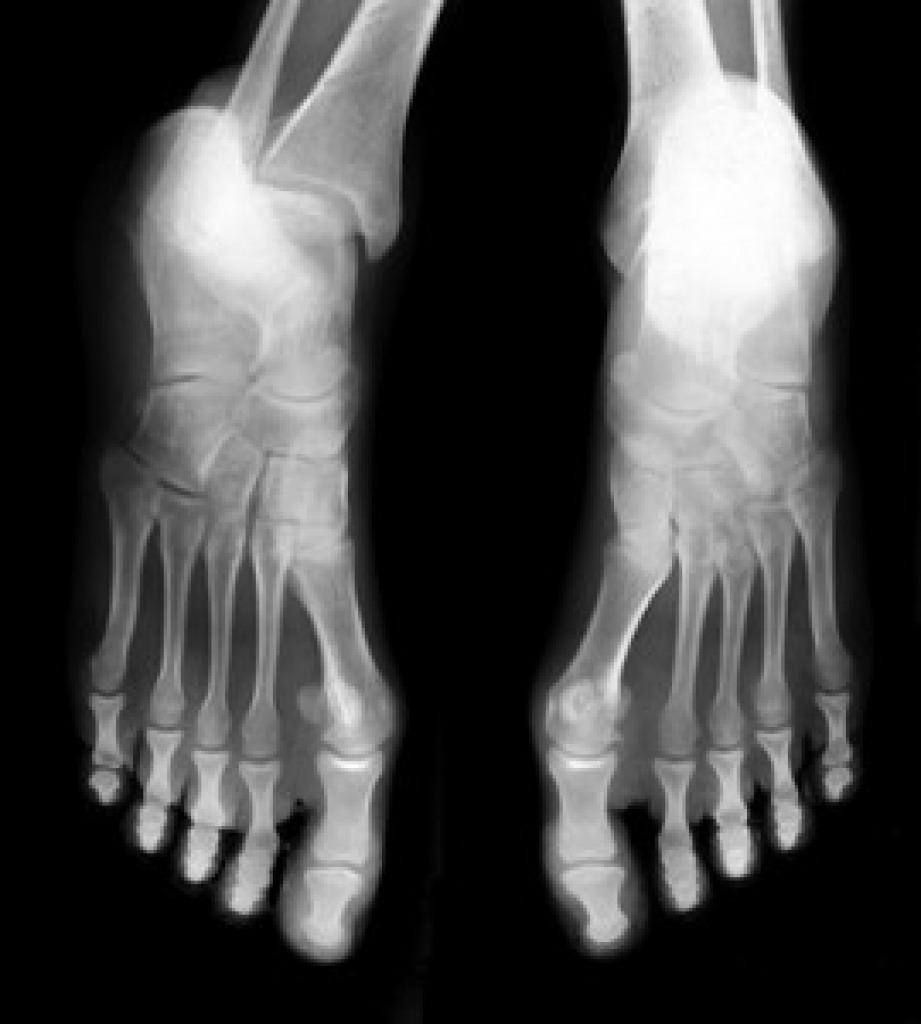

What Is Plantar Fasciitis?

Plantar fasciitis is the inflammation of the thick band of tissue that runs along the bottom of your foot, known as the plantar fascia, and causes mild to severe heel pain.